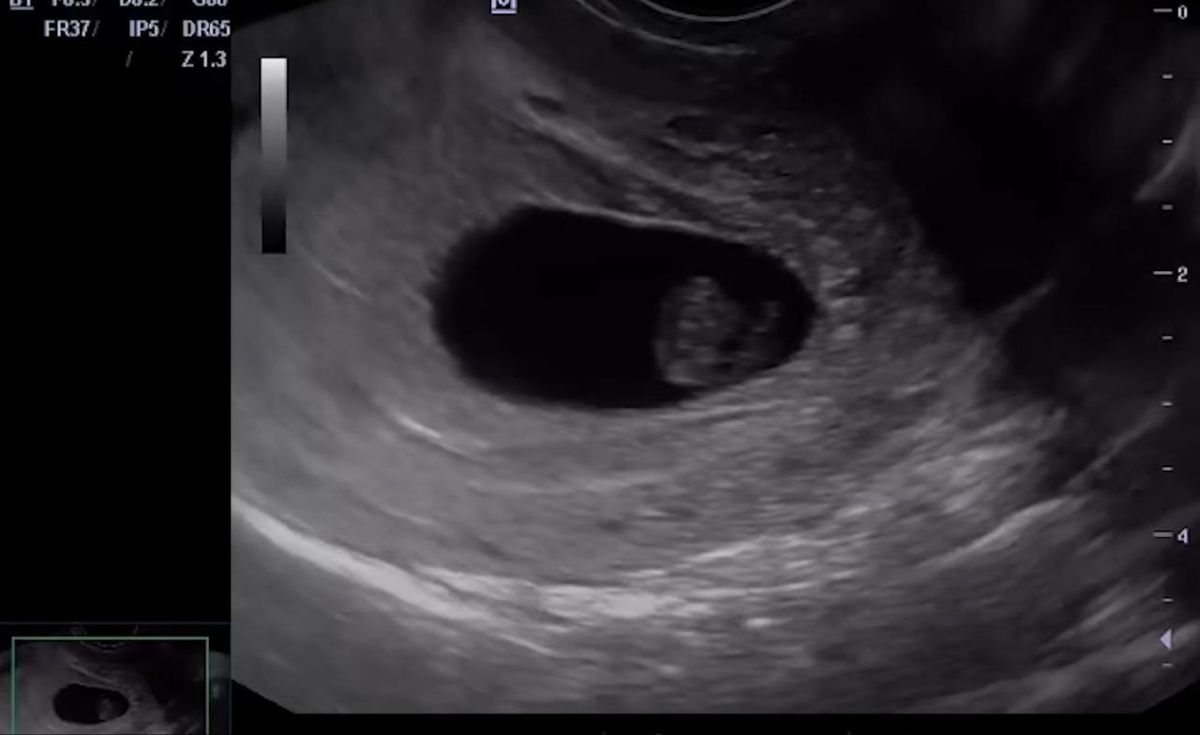

В мае, когда менструация так и не наступила, Валентина решила сделать тест на беременность. И вновь результат оказался положительным. Она не могла поверить своим глазам и думала о самых худших сценариях: вдруг это опухоль или серьёзное заболевание. Она обратилась в частную клинику, где врач УЗИ с недоумением сообщил ей: "Вы беременны, срок около 14-15 недель". Валентина была в шоке и даже выругалась от неожиданности, пытаясь объяснить врачу, что это невозможно. Но монитор показывал другое — изображение малыша с руками и ногами.

Фотография повторного УЗИ Валентины